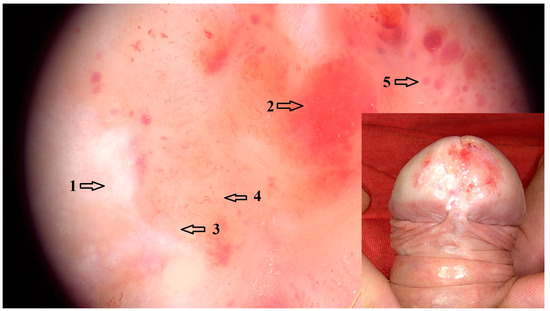

Vascular dermoscopic features that were significantly associated with LSBP included dotted vessels in an unspecific distribution (OR = 5.89 95% CI: 1.76–19.70; p = 0.033), linear vessels (OR = 32.70 95% CI: 3.58–299.00; p < 0.001) and linear curved vessels (OR = 11.60 95% CI: 2.42–55.10, p = 0.009) in an unspecific distribution, as well as decreased vascular density (OR = 1353.00 95% CI: 52.70–34,769.00; p < 0.001). Other dermoscopic features that were positively associated with LSBP cases included white structureless areas (OR = 139.00 95% CI: 7.79–2466.00; p < 0.001) and white lines (OR = 5.88 95% CI: 1.53–22.60; p = 0.038). Particularly white lines in an unspecific arrangement were a common feature of LSBP (OR = 5.00 95% CI: 1.36–18.40; p = 0.086), although association with this arrangement was not statistically significant. Red globules (OR = 29.70 95% CI: 1.45–607.00; p = 0.049), as well as purple globules (OR = 54.1 95% CI: 2.81–1043.00; p < 0.001) were dermoscopic representations of purpura in LSBP (Figure 3). White dots and globules, although a common feature of LSBP, were not statistically significantly associated (OR = 9.08 95% CI: 1.50–54.90; p = 0.086).

Figure 3. Dermoscopic image (magnification 20×) of LSBP with white (1) and red (2) structureless areas, white lines (3), sparse and unspecifically arranged curved linear vessels (4) and red and purple globules (5). Clinical image of LSBP with erythema and white areas on the glans as well as purpura.